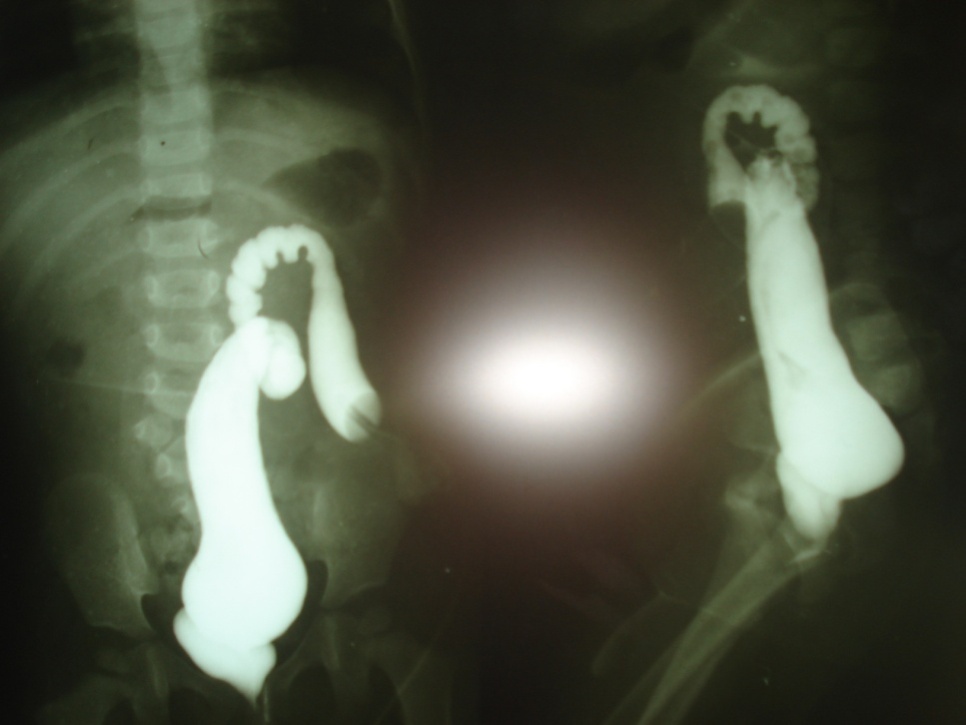

A six-year-old female presented for

definitive procedure of persistent cloaca (Fig. 1). She had colostomy on 5th

day of life. Ultrasound of abdomen was

reported as normal. Distal colostogram showed high

recto-cloacal fistula (Fig. 2).

Figure 2: Distal loopogram showing high insertion of rectum

into common channel.